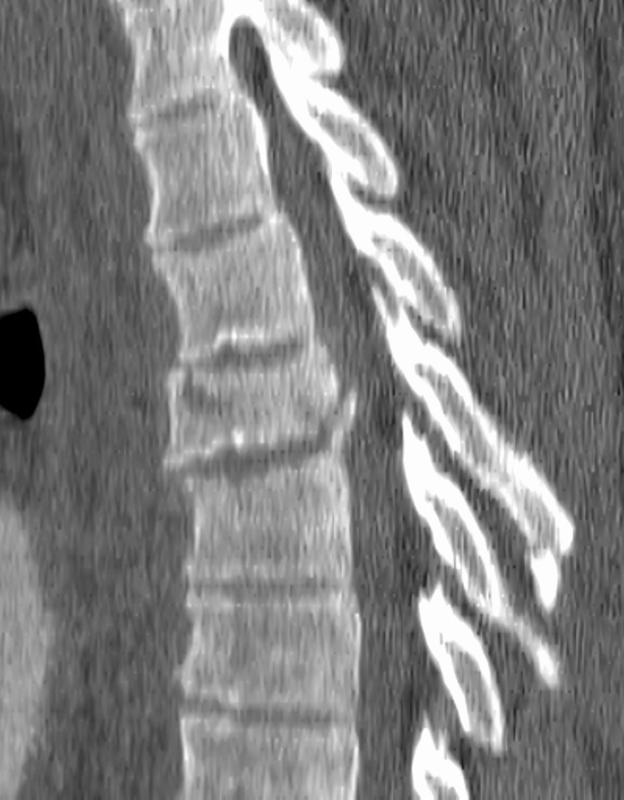

Gallery Blunt Chest Trauma Spine trauma Case 4d

Case 4d